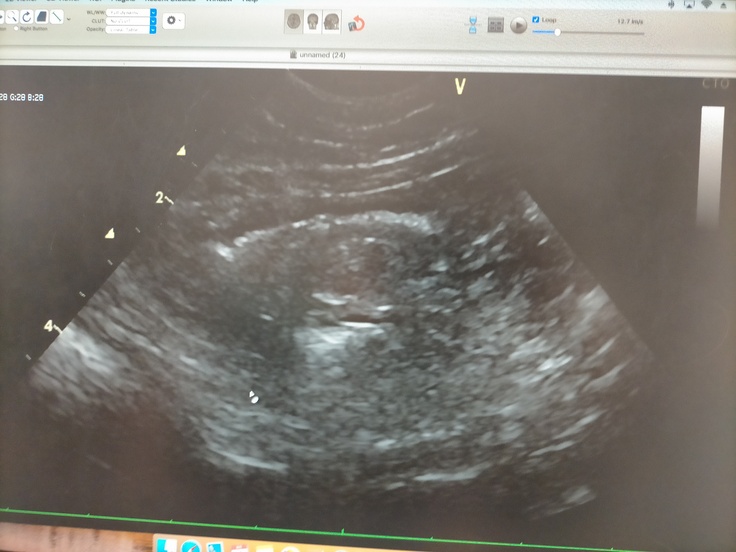

モカちゃん今日は1ヶ月検診でした!🏥

今日の検査の結果…

腸の中の腫れなし!内臓も綺麗!心配してた膀胱(前回脂肪と思われる白いモヤがあったり、おしっこの間隔が長い日があり)も問題なしで、

全身状態は非常に良く、再発の影もなしとのことで、遂に先生から

「寛解です!」